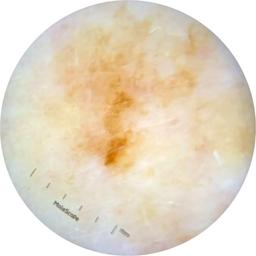

ISIC_9965024

Clinical

Field Value

acquisition_day 129

age_approx 75

anatom_site_1 Head and neck

anatom_site_general head/neck

concomitant_biopsy False

diagnosis_1 Benign

diagnosis_confirm_type single image expert consensus

family_hx_mm False

image_manipulation instrument only

image_type dermoscopic

lesion_id IL_4355888

patient_id IP_7946204

personal_hx_mm True

sex female